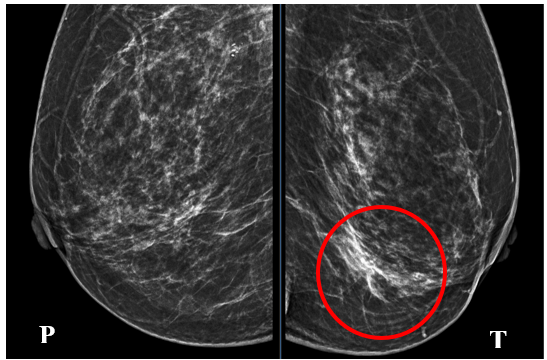

Cách vào viện 5 ngày, bệnh nhân xuất hiện chảy máu núm vú trái, máu đỏ tươi, số lượng ít, không đau vú, không tự sờ thấy khối u ở vú, không nôn, không sốt, không đau tức ngực. Bệnh nhân đi khám tại Bệnh viện Bạch Mai được chụp X-quang tuyến vú 2 bên cho hình ảnh tuyến vú trái có đám tăng đậm độ bất xứng góc 1/4 dưới trong – BIRADS 4, không thấy các vi vôi hóa nghi ngờ ác tính.

Hình 1: X-quang tuyến vú 2 bên. Hình ảnh đám tăng đậm độ bất xứng ¼ dưới trong bên trái)